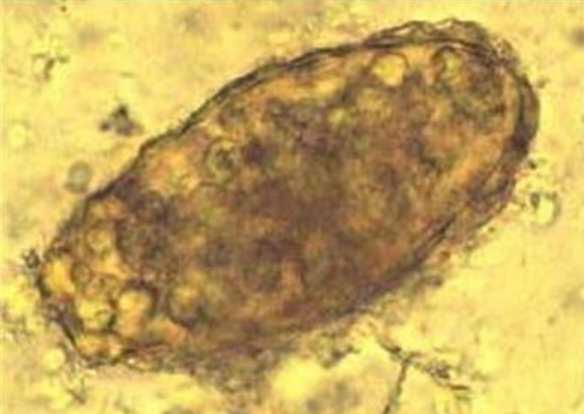

人体粪便中的蛔虫卵分受精卵和未受精卵。受精卵呈椭圆形,大小约为(45~75)μm ×(35~50)μm ,卵壳较厚。卵壳外常有一层由子宫分泌物形成的凹凸不平的蛋白质膜,被宿主胆汁染成棕黄色。卵内含有一个大面圆的受精卵细胞,在其两端于卵壳间可见新月形空隙。虫卵在外界发育,胚细胞不断分裂,最后形成含幼虫的感染期虫卵。

未受精卵呈长椭圆形,大小约为(88~94)μm ×(39~44)μm 。卵壳与蛋白质膜均较受精蛔虫卵薄。卵内充满大小不等的折光颗粒。卵壳周围蛋白质膜脱落后,成为脱蛋白膜的蛔虫卵。未受精卵没有发育的可能,也没有感染致病的能力。